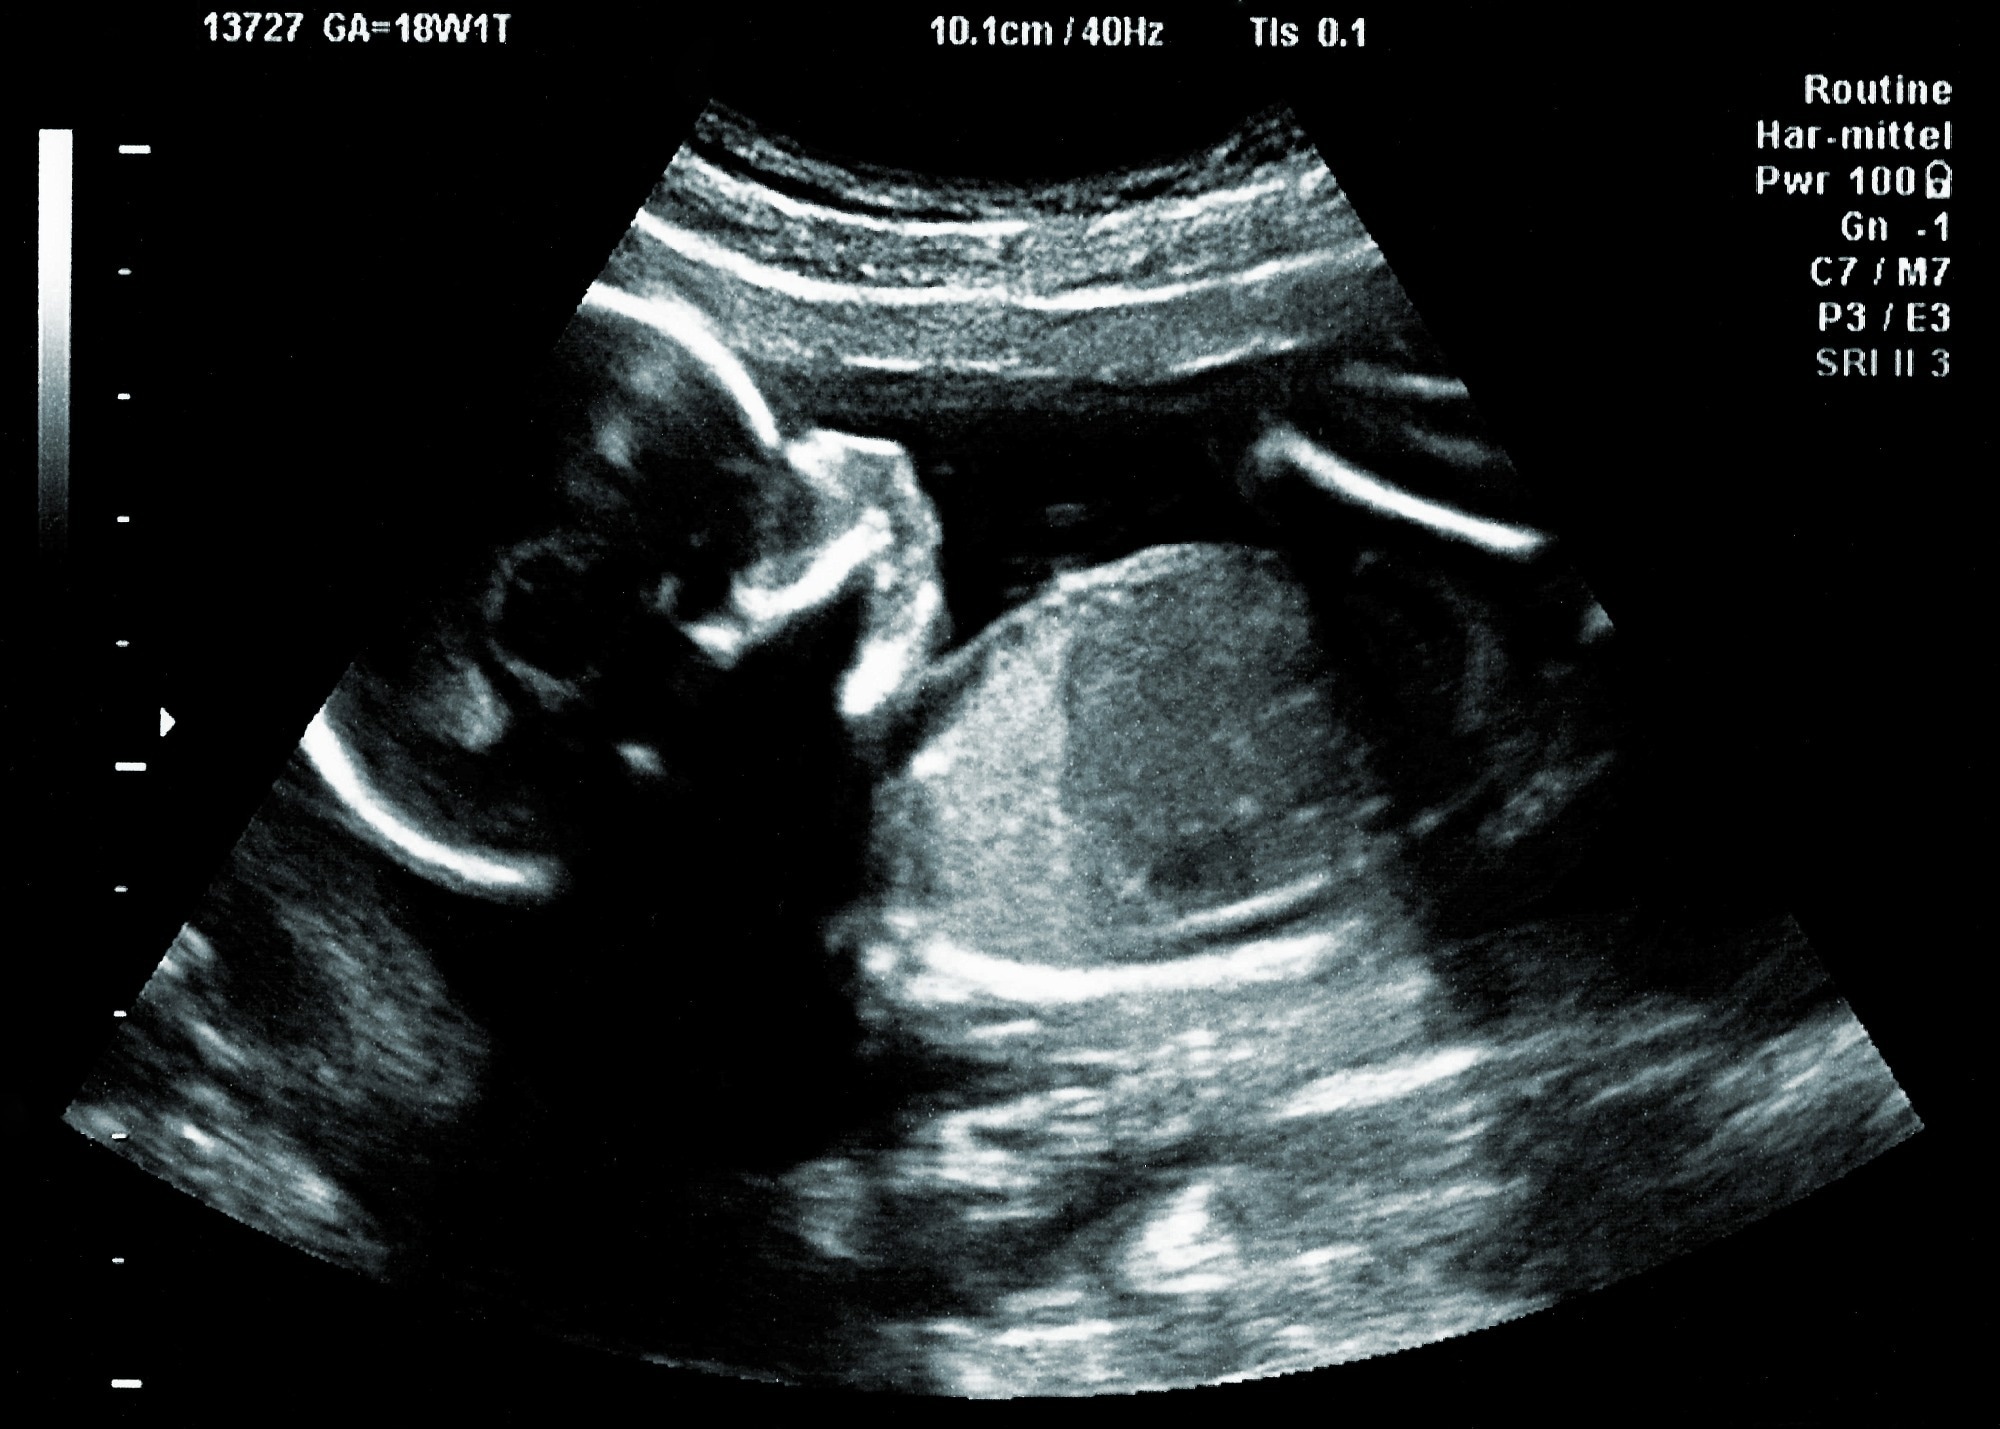

Study: Placental nanoparticle-mediated IGF1 gene therapy corrects fetal growth restriction in a guinea pig model. Image Credit: r.classen / Shutterstock.com

Guinea pigs were divided into different treatment groups, including control, maternal nutrient restriction (MNR) diet, and MNR + IGF1 groups. After a two-week acclimation period and proper diet program, female guinea pigs were anesthetized, during which either the nanoparticle or sham treatment was delivered to the placenta through ultrasound-guided intra-placental injection. This treatment was repeated every eight days starting from gestation day (GD) 36.